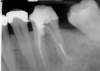

(1.) Preoperative radiograph of teeth Nos. 30 and 31 exhibiting previously treated, symptomatic apical periodontitis and pulp necrosis with a chronic apical abscess and an endodontic-periodontic lesion, respectively.

Figure 1